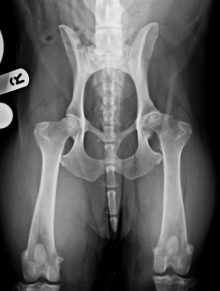

Gus is doing well following bilateral hip replacements

It was great to see Gus back in the clinical last week for his x-rays 6 weeks after the ...